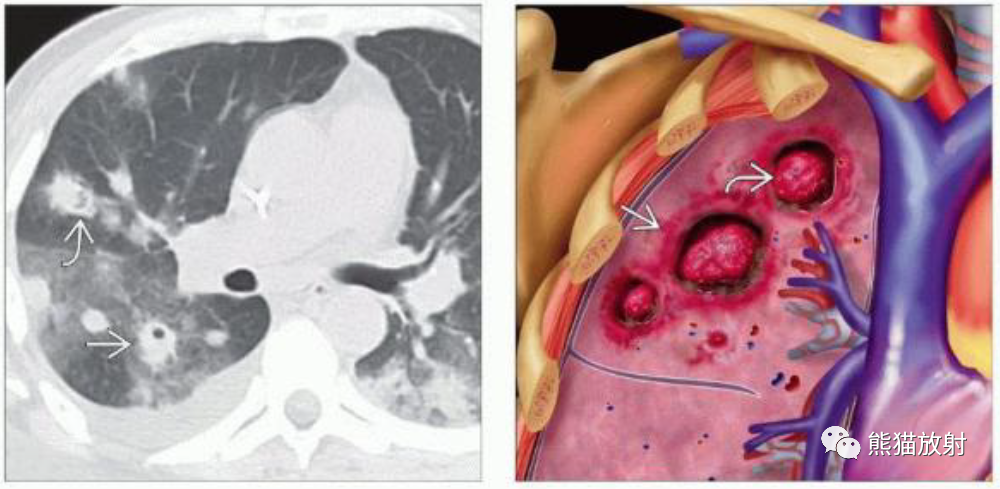

(左)急性髓细胞性白血病和侵袭性曲霉病患者,轴位NECT显示多个肺结节,一些有空洞(直箭),周围有磨玻璃影。其中一个结节中的空气新月征(弯箭)勾勒出局部肺坏死,这是血管侵袭性真菌感染的特征。

(右)图示为侵袭性曲霉病的典型特征,特征是多灶性空洞性病变,可见空气新月形征包围的坏死肺和周围出血所致的晕征。